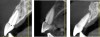

Fig 4. (Left) Grade I socket with an intact buccal plate demonstrating less than 25% bone loss; (Center) Grade II socket showing fissure, dehiscence, and approximately 50% buccal plate loss; (Right) Grade III socket with more than 50% buccal plate loss.

Figure 4

Fig 5. Sagittal cross-sections of CBCT images depicting Grade I (Left), Grade II (Center), and Grade III (Right) sockets. Note the level of the buccal plate relative to the cementoenamel junction that is elucidated by this cross-cut.

Figure 5